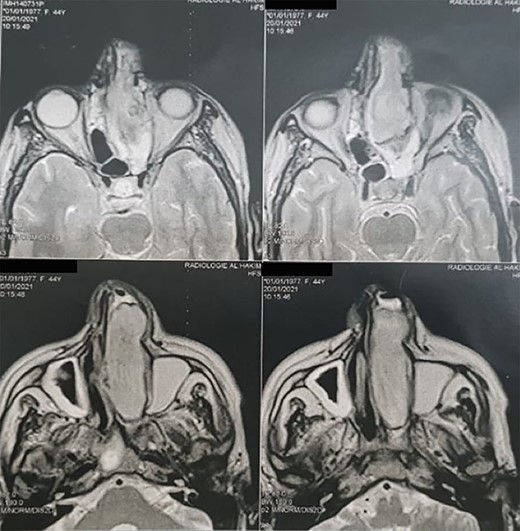

A 45-year-old patient with no significant pathological history was admitted to the otorhinolaryngology department in March 2021. She had a 7 months history of purulent rhinorrhea, occasional epistaxis associated with swelling of the left nasal cavity gradually increasing in size. Clinical examination found a 6 cm whitish firm mass, filling the left nasal cavity, firm and painful on palpation and deflecting the dorsum and tip of the nose to the right. A facial magnetic resonance imaging (MRI) was performed showing a tissue process in the left nasal cavity (Fig. 1). An initial biopsy performed suggested a synovialosarcoma. The patient then underwent surgical resection preceded by two sessions of chemotherapy, allowing tumor size reduction.

Head MRI showing a filling of the left nasal cavity by a neoplastic process.